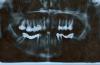

GASS Опубликовано 22 декабря, 2008 Поделиться Опубликовано 22 декабря, 2008 (изменено) Уважаемые врачи! Подскажите пожалуйста какое в моём случае протезирование зубов лучше?Мосты надо менять , что лучше опять мосты или импланты?Врач предлагает удалить четвёрку с лева там киста и с права так как ему корень не очень нравиться. Обточить клыки и одеть мосты на них, но я боюсь что это не будет держаться. да и обтачивать здоровые зубы жалко, у меня их и так мало. Неужели мост на 5 зубов сможет удержаться на клыке и семёрке когда трёх зубов небудет?Буду признательна за ответ.Тёмная фотка, пока не знаю как улучшить, передние нижние зубы впорядке, здоровые и без пломб, верхние передние тоже пока не требуют коронок. Изменено 22 декабря, 2008 пользователем GASS Ссылка на комментарий

GASS Опубликовано 22 декабря, 2008 Автор Поделиться Опубликовано 22 декабря, 2008 (изменено) Это целый последовательный комплекс диагностики смыкания зубных рядов, проведение мероприятий по улучшению и правильности их смыкания.После всего этого - можно с большой долей вероятности спланировать хорошую и качественную работу.Ну, и сделать ее. Вы имеете ввиду исправить прикус? Ортодонтическое лечение? Я правильно поняла? Я консультировалась у ортадонта, врачь сказал что лучше не трогать, зубы в низу здоровые, но как поведут себя после брекетов неизвестно, а в моём случае рисковать нельзя и так зубов мало.Внизу два моста нужно менять, стоят очень давно, справа мост сломался, менять нужно срочно. Сделаны мосты из железа и пластмассы. Врач сказал что металокерамику 4 с права не выдержит её нужно удалять и ставить мост с 7 по 3. Это нормально, или это опасно для опорных зубов? Темболее что 3-здоровый зуб без пломб. Пожалуйста подскажите, что делать и возможна ли в моём случае имплантация? Изменено 22 декабря, 2008 пользователем GASS Ссылка на комментарий